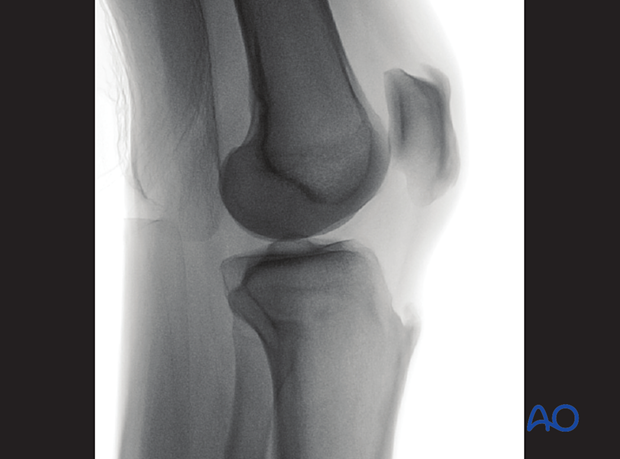

To obtain the optimal lateral view of the distal femur:

The optimal lateral view to the proximal tibia is obtained when:

The following lines and landmarks are seen in the lateral view of the proximal tibia:

The lateral view of the proximal tibia is particularly useful to identify: